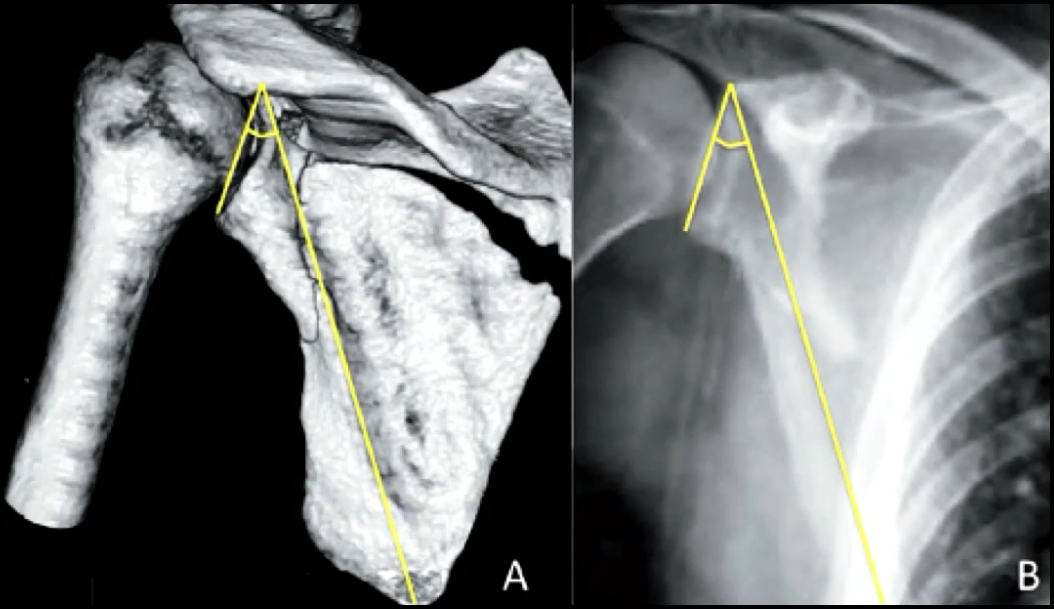

Avaliação ângulo Glenopolar ?

Ângulo entre:

* Linha da margem inferior até margem superior da glenoide

* Linha entre margem superior da glenoide até ápice inferior da escápula

Se < 20º → Pensar em TTO Cirúrgico